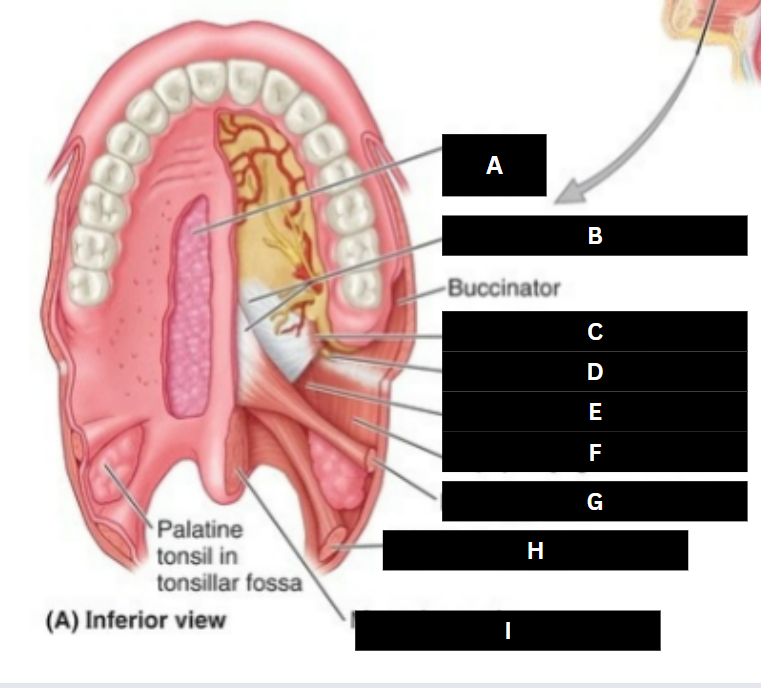

Palatine glands

A

Palatine aponeurosis

B

Tensor veli palatini

C

Pterygoid hamulus

D

Levator veli palatini

E

Superior pharyngeal constrictor

F

Palatoglossus

G

Palatopharyngeus

H

Musculus uvulae

I